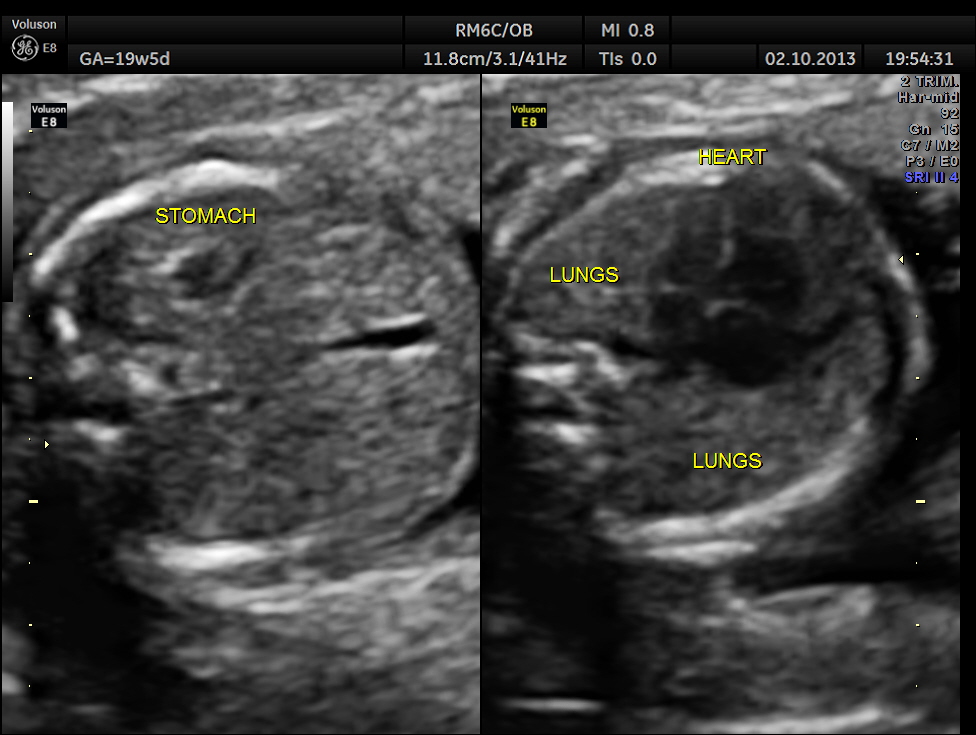

The following pictures show that the left ventricle appears smaller than the right ventricle. The situs is normal.

A normal 3 vessel view and 4 chamber view are given below.